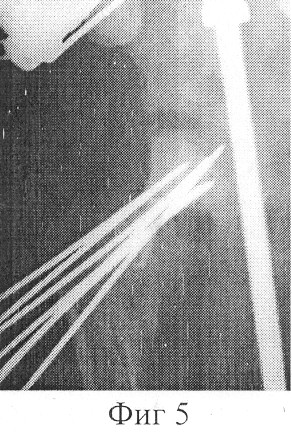

Фиг.5 – копия рентгенограммы пациента после окончания коррекционного разворота фрагментов;

Больной проведено оперативное вмешательство. В операционной под внутривенным наркозом через крыло подвздошной кости проведено 4 спицы, которые фиксированы в дуге и натянуты. Через дистальный метафиз бедра проведено 3 спицы, которые фиксированы в 3/4 кольца и натянуты. На границе верхней трети и средней трети бедра в сагиттальной плоскости проведены две перекрещивающиеся спицы с упорными площадками, фиксированы в дуге, которая соединена с опорой на дистальном метафизе бедра с помощью стержней. Бедро установлено в положение отведения 30°, разгибания 180° и внутренней ротации 40°. Через дистальный отдел шейки в сагиттальной плоскости проведены две перекрещивающиеся под углом 15° спицы с упорными площадками навстречу друг другу, которые фиксированы в дуговой опоре и натянуты. Опору соединили с дугой на подвздошной кости стержнями Через разрез 4 см по передней поверхности бедра в вертельной области произведена С-образную остеотомия бедра от верхне-наружнего края шейки до верхнего края малого вертела. Дистальный отдел бедренной кости приведен на 30° и ротирован внутрь на 25°. Опоры, установленные на шейке бедра и на границе верхней и средней трети бедра соединены стержнями с шарнирными устройствами. Стержни установлены в направлении сверху вниз изнутри кнаружи перпендикулярно линии, касательной к плоскости входа во впадину. Наложены швы на рану. С шестого дня в течение 48 суток производили дистракцию в зоне остеотомии 0,5 мм в сутки (Фиг.4). После окончания дистракции в операционной под наркозом через через вертельную область, зону удлинения, шейку и головку бедра проведены 6 спиц, свободные концы которых фиксированы к опоре, расположенной на границе верхней трети и средней трети бедра (Фиг.5). Удалены спицы, проходившие через шейку бедренной кости. Продолжительность фиксации фрагментов бедренной кости в корригированном состоянии 90 дней. После демонтажа аппарата и удаления спиц проведен курс восстановительного лечения.